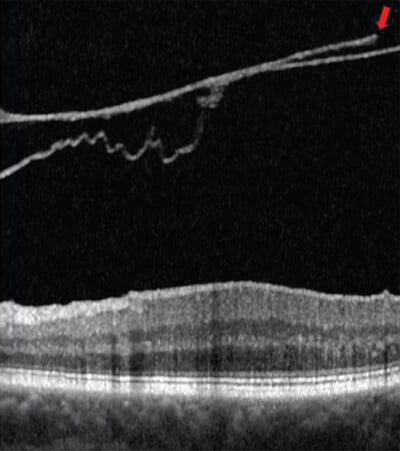

A break in the posterior vitreous cortex appears (arrow)

Image courtesy: Jim Williamson, OD